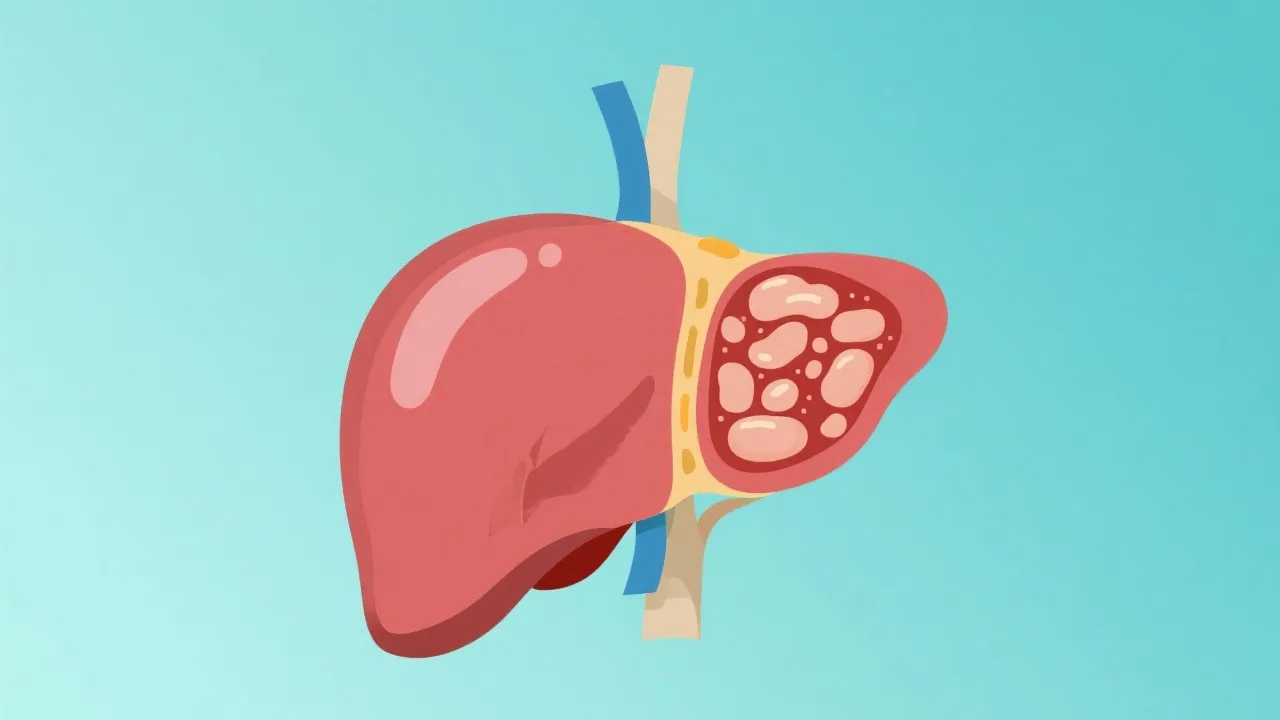

Non-Alcoholic Fatty Liver Disease, commonly referred to as NAFLD, represents a spectrum of liver conditions characterized by the accumulation of excess fat in liver cells. Unlike other forms of liver diseases, NAFLD occurs in individuals who consume little to no alcohol. It is associated with obesity, insulin resistance, high blood sugar, and high levels of fat in the blood. The liver, an essential organ in the body, plays a critical role in various metabolic processes, including detoxification, protein synthesis, and the production of biochemicals necessary for digestion. When fat accumulates in the liver, it can disrupt these functions and potentially lead to serious health complications.

Globally, NAFLD is becoming a leading cause of liver disease, representing a significant burden on healthcare systems. The rise in obesity rates and metabolic syndromes in various populations, especially in Western countries, has resulted in this increased prevalence. NAFLD can progress to Non-Alcoholic Steatohepatitis (NASH), a more severe form of the disease that can lead to liver fibrosis, cirrhosis, and even hepatocellular carcinoma. Statistics indicate that the prevalence of NAFLD ranges from 25% to 30% in the general population, and this number is expected to grow. This epidemic is not solely limited to adults; children are increasingly being diagnosed with NAFLD due to the correlating rise in childhood obesity, making this an urgent public health concern.

The complexity of NAFLD necessitates innovative approaches to understand and develop therapeutic strategies. This is where NAFLD models in drug discovery come into play. Researchers utilize these models to mimic the progression of NAFLD, offering insights into physiological changes and testing new drug formulations before moving to human trials. The development of NAFLD models can accelerate the understanding of the disease and streamline the drug testing process, reducing the time and resources needed to bring effective treatments to market. As NAFLD is a multifactorial disease, a multidimensional approach is essential in creating these models that encompass genetic, environmental, and lifestyle factors impacting liver health.